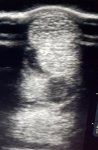

Picture 1 December 2019, around the 28th December to be precise. Damaged tendon fibres showing as a large hole (check ligament injury in 23yr old). Ice therapy started on the 21st December which is the day I rang the vets to inform them my horse had gone dramatically lame out on a hack and would they come and advise as no heat/swelling could be felt. Less than an hour later both heat and swelling were present. It turned out to be a check ligament. I started icing after the vet had gone and continued twice a day until second week in Feb as I was on furlough. I was mental with the ice, I would ice using an ice cup. Then around an hour later I would ice using ice vibe boots. I also used LW ultrasound for 10 mins once a day, and bandaged both front legs. Also gave anti inflammatories and my horse went on box rest.